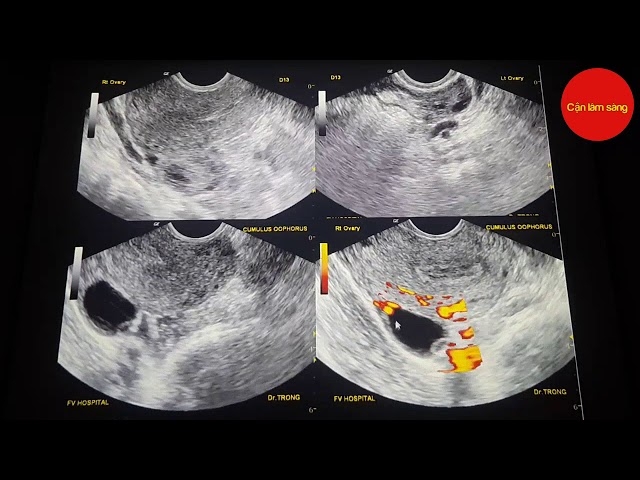

Vậy, khi Trứng đã Rụng Siêu âm Có Thấy Không những dấu hiệu gián tiếp nào? Bác sĩ sẽ tìm kiếm những thay đổi sau trong buồng trứng và vùng tiểu khung của bạn:

Sự biến mất của nang trứng trội: Trước khi rụng, siêu âm sẽ thấy một nang trứng lớn, tròn, căng mọng. Sau khi rụng, nang trứng này sẽ biến mất hoặc xẹp đi, thay vào đó có thể là một cấu trúc xù xì, bờ không đều.

Sự xuất hiện của thể vàng (Corpus Luteum): Đây là dấu hiệu quan trọng nhất. Sau khi trứng rụng, phần vỏ nang trứng còn lại sẽ nhanh chóng phát triển thành một cấu trúc gọi là thể vàng. Thể vàng có nhiệm vụ sản xuất progesterone, hormone cần thiết để chuẩn bị cho tử cung đón nhận phôi thai. Trên siêu âm, thể vàng thường có hình dạng không đều, bờ dày, và có thể có một hốc nhỏ ở giữa.

Dịch tự do trong túi cùng: Khi nang trứng vỡ ra, một lượng nhỏ dịch nang có thể chảy vào khoang bụng, đặc biệt là vùng túi cùng (không gian phía sau tử cung). Lượng dịch này thường rất ít và tự tiêu biến, nhưng việc phát hiện dịch tự do có thể là một bằng chứng gián tiếp khác của quá trình rụng trứng vừa diễn ra.